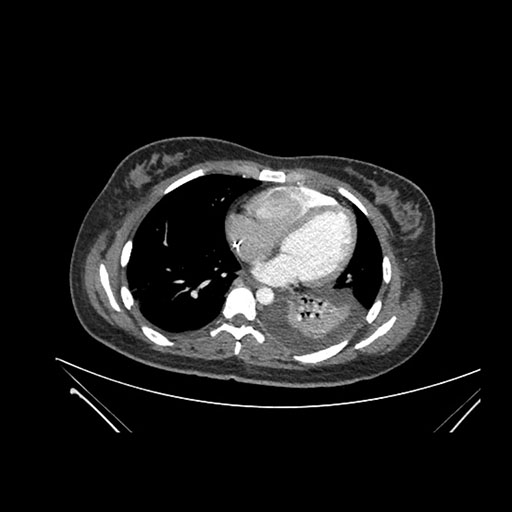

Imaging Analysis

Look through the patient's CT scan to identify any areas of concern for the necessary procedure.

Axial Arterial

Based on initial findings, which issue(s) would you be most concerned about?